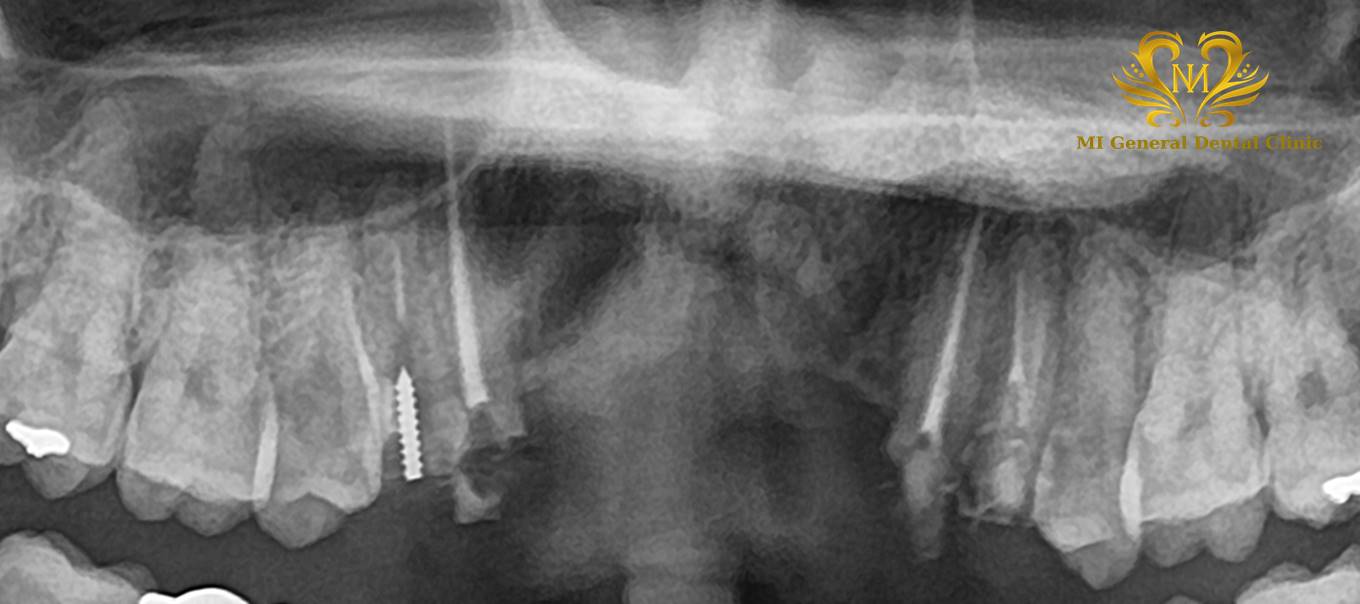

治療前

前歯4本が欠損しています。

治療後

インプラント体とセラミックスの前歯のセット後の状態です。

| 治療内容 | 前歯のブリッジの支えが痛くなり来院。ブリッジを除去し、仮歯に置き換えて根管治療。その後、前歯4本欠損のインプラント治療及び骨造成。その後、仮歯の調整等をしてセラミックスのインプラント上部構造装着。 |